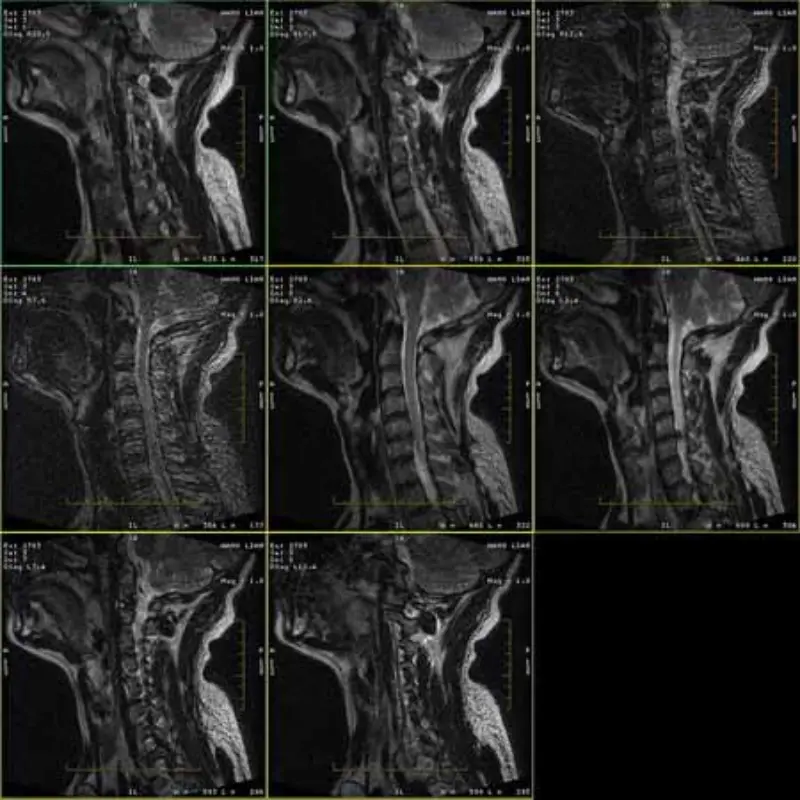

Imagines FRFSE et GRE protocolla larvae habent et interdum in una serie SNR imagines humiles apparent. Sed SE protocollo imagines normales sunt.

Vide quaeso imagines attach.

1. Artificia haec tantum occurrunt in protocollis FRFSE et GRE, sed SE protocolli

imagines numquam apparent. Caput SPT Fac Velox reprehendo, caput SNR marginalis est (circiter 8.2).